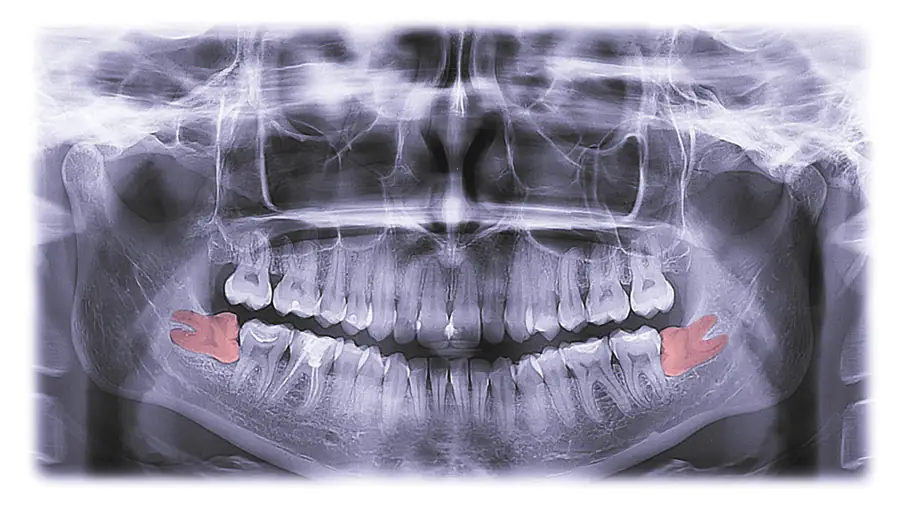

For the study, 38 patients ages 18 to 30 completed a 66-item questionnaire before surgery assessing their expectations about pain, functional limitations, complications, recovery, and social impact. Participants were consecutive patients referred for their first extraction of at least one mandibular third molar, with or without maxillary third-molar removal, they wrote.